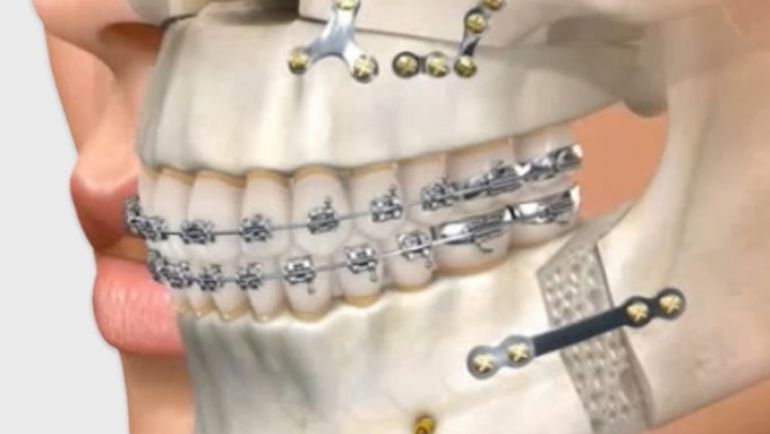

Cirugías para prótesis o planificación ortodóncica.

Usamos radiografías digitales, tomografía 3D (Cone Beam) y simulaciones precisas.